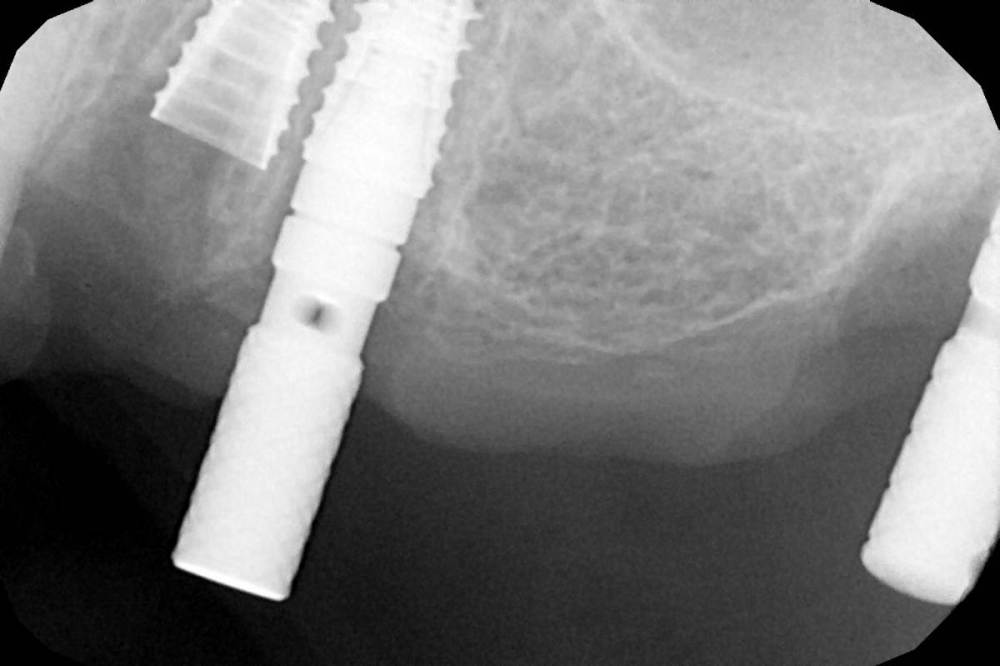

Дмитрий Л. Опубликовано 17 января, 2022 Поделиться Опубликовано 17 января, 2022 Ничего страшного, что близко, просто теперь работу лучше на времянках сдавать хотя бы на год, чтобы оценить стабильность кости. Если будут проблемы, то один импл заглушить. Ссылка на комментарий

major Опубликовано 17 января, 2022 Поделиться Опубликовано 17 января, 2022 Время есть. Место тоже. Может подумаете о переустановке хотя бы 2.4 мезиальнее? Ссылка на комментарий

Женька Опубликовано 17 января, 2022 Автор Поделиться Опубликовано 17 января, 2022 @Дмитрий Л. корешок, был удалён @major да, возможно заглушу 2.5 и 2.6 поставлю, благо 7мм там есть Ссылка на комментарий

major Опубликовано 17 января, 2022 Поделиться Опубликовано 17 января, 2022 @Женька не кажется что 2.4 слишком дистально установлен? Или это угол такой на фото? Переустановить 2.4 и ничего глушить не надо. 1.5-2 мм судя по Рг и фото есть. Ссылка на комментарий